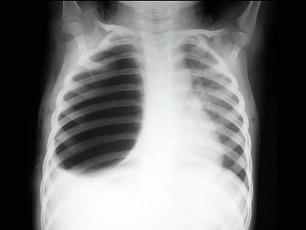

女,9岁,呼吸困难半月余,结合图像,最可能的诊断是?(?)A.气胸B.胸腔积液C.肺大泡D.液气胸E.肺气肿

问题 女,9岁,呼吸困难半月余,结合图像,最可能的诊断是?(?)

选项 A.气胸 B.胸腔积液 C.肺大泡 D.液气胸 E.肺气肿

答案 C